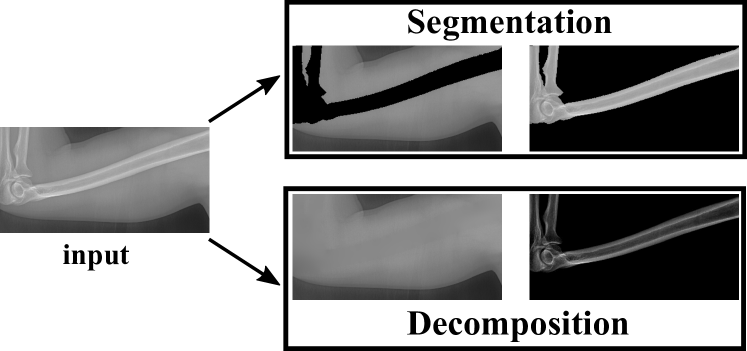

Refer to caption

Figure 3: Our method simultaneously performs bone enhancement and bone suppression.

Different from the bone enhancement or suppression, we propose to decompose the input X-ray image into one bone image and one soft tissue image. Such task is named as Bone and Soft Tissue Decomposition (BSTD). We construct a new mathematical model that can effectively decompose the soft tissues in X-ray images. Our method decomposes the input X-ray image into background image (soft tissue) and bone image. Be aware the difference between our model and the bone segmentation task. Bone segmentation separates the imaging domain into bone region and background region (without overlap). However, our background and bone images share the same imaging domain (exactly overlapped with the same imaging domain). Such difference is illustrated in Fig. 4.

Figure 4: Our task is different from the classical bone segmentation.